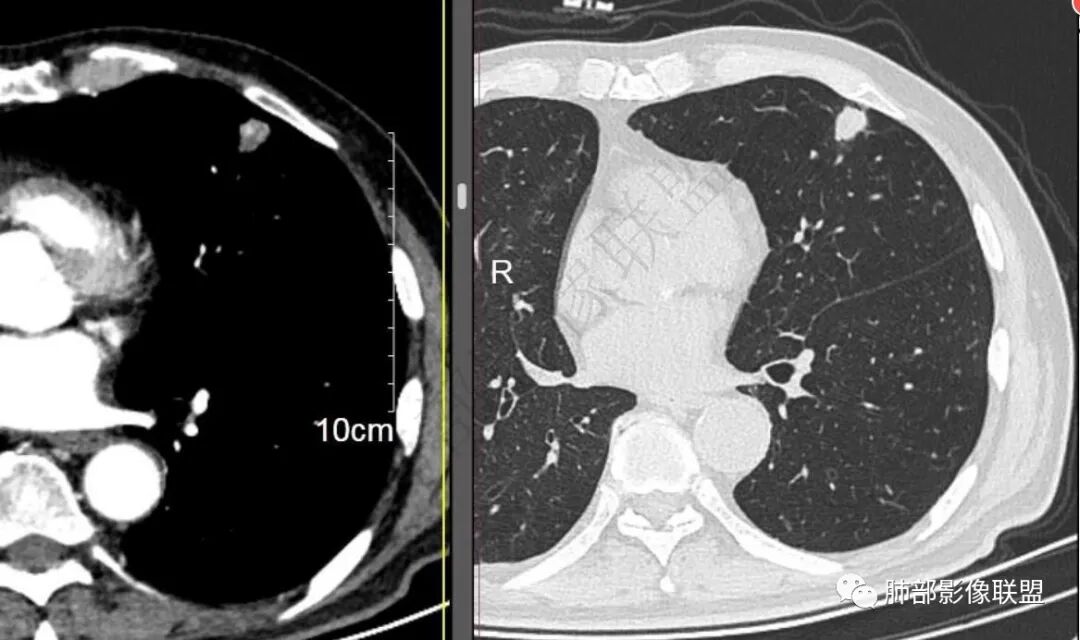

二..发现左肺上叶舌段实性密度小结节影,不规则略呈半环形,边界清楚,未见分叶、毛刺及磨玻璃晕。未见卫星病灶。

9个月后病灶明显增大,边缘较平直,部分膨隆,锁扣样外观,仍旧缺乏典型深分叶及张力,未见胸膜凹陷。

再1个多月后病灶继续增大,较明显不均匀强化,肺门一侧见低密度区。病灶边缘相对不清,可见毛刺。

三.病程脉络相当清楚,即病灶进行性增大,易想到新生物或转移瘤,但经验上分析增长速度显然太快,尤其是对于原发肺腺癌或者肺鳞癌而言,单发转移瘤也较少这样的进展速度。

四.单就影像而言,病灶肿瘤特征不够充分,恶性肿瘤病史,隐球菌等特殊感染确实不能排除。